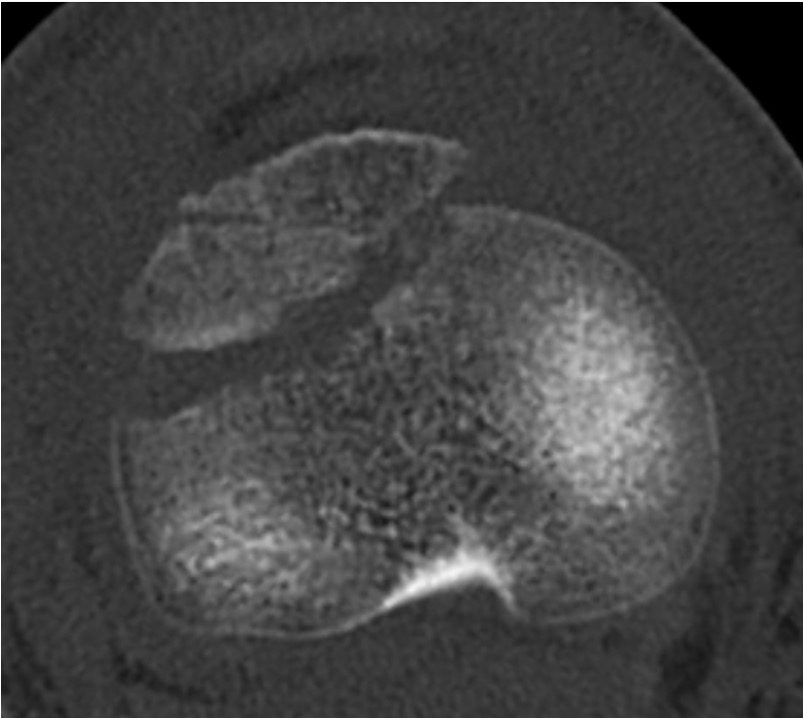

CT / MRI scan

CT scan - ensure fracture doesn't involve the physis / disrupt articular surface

MRI scan - patella tendon injury / periosteal sleeve avulsion

Comminuted Type III